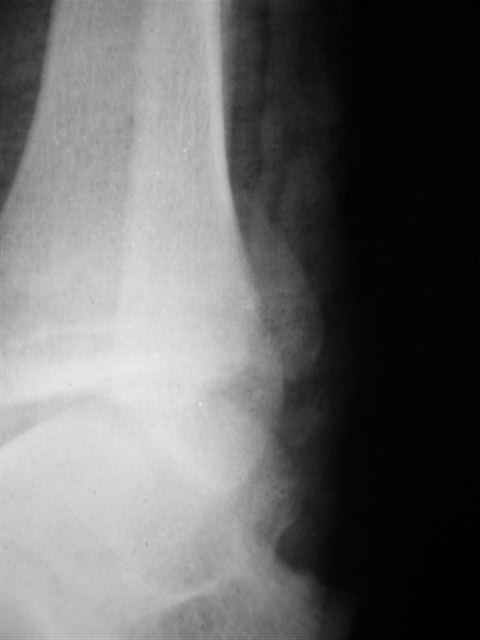

В первом письме я упомянул о закрытом повреждении правого голеностопного сустава, эверсионно-пронационный механизм травмы - перелом внутренней лодыжки( поперечный, на уровне суставной щели) и отрывной перелом бугорка Chaput. После обработки открытых переломов бедра и большеберцовой кости в эту же сессию перелом внутренней лодыжки фиксировал двумя расходящимися спицами, бугорок Chaput двумя тягловыми винтами 3,5 мм. Раны заживают благополучно. Учитывая повреждение наружной группы мышц, активное разгибание в голеностопном суставе ограничено. Пассивная + пассивно-активная мобилизация голеностопного сустава с физиотерапевтом.